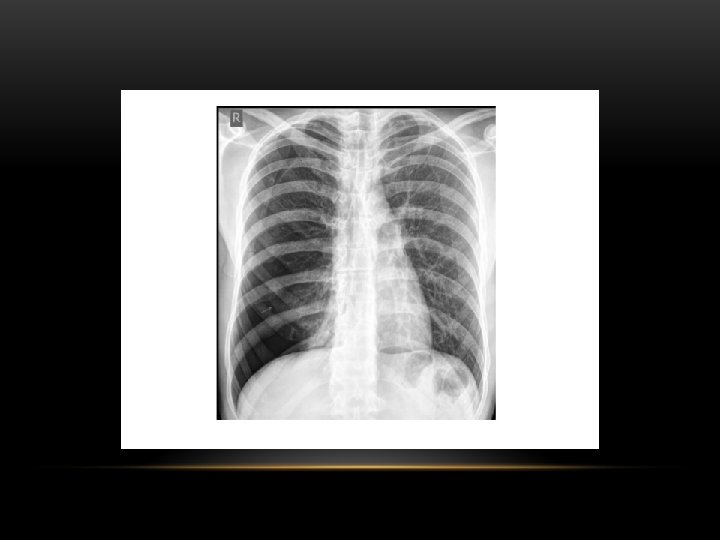

Pneumothorax is air in the pleural space. Radiological criteria: Air (black) in pleural space. No lung markings in pleural space. Recognition of atelectatic lung (lung margin). The lung recoils to a resting state as the negative pressure in the pleura is lost (relaxation atelectasis).

Pneumothorax • No vascular markings on right • No shift of mediastinum to left • Atelectasis right lung • Increased haziness on left: Diversion of entire cardiac output • Small fluid level near costophrenic angle: Hydro pneumothorax